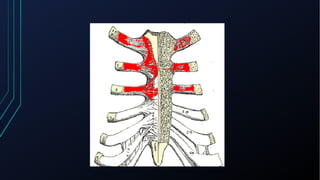

Dor torácica pode ter diversas causas, incluindo cardíacas como síndrome coronariana aguda, dissecção de aorta e pericardite, e não cardíacas como problemas pulmonares, musculoesqueléticos e do trato gastrointestinal. É importante avaliar a história clínica, características da dor e exame físico para identificar a possível causa e orientar o tratamento adequado.